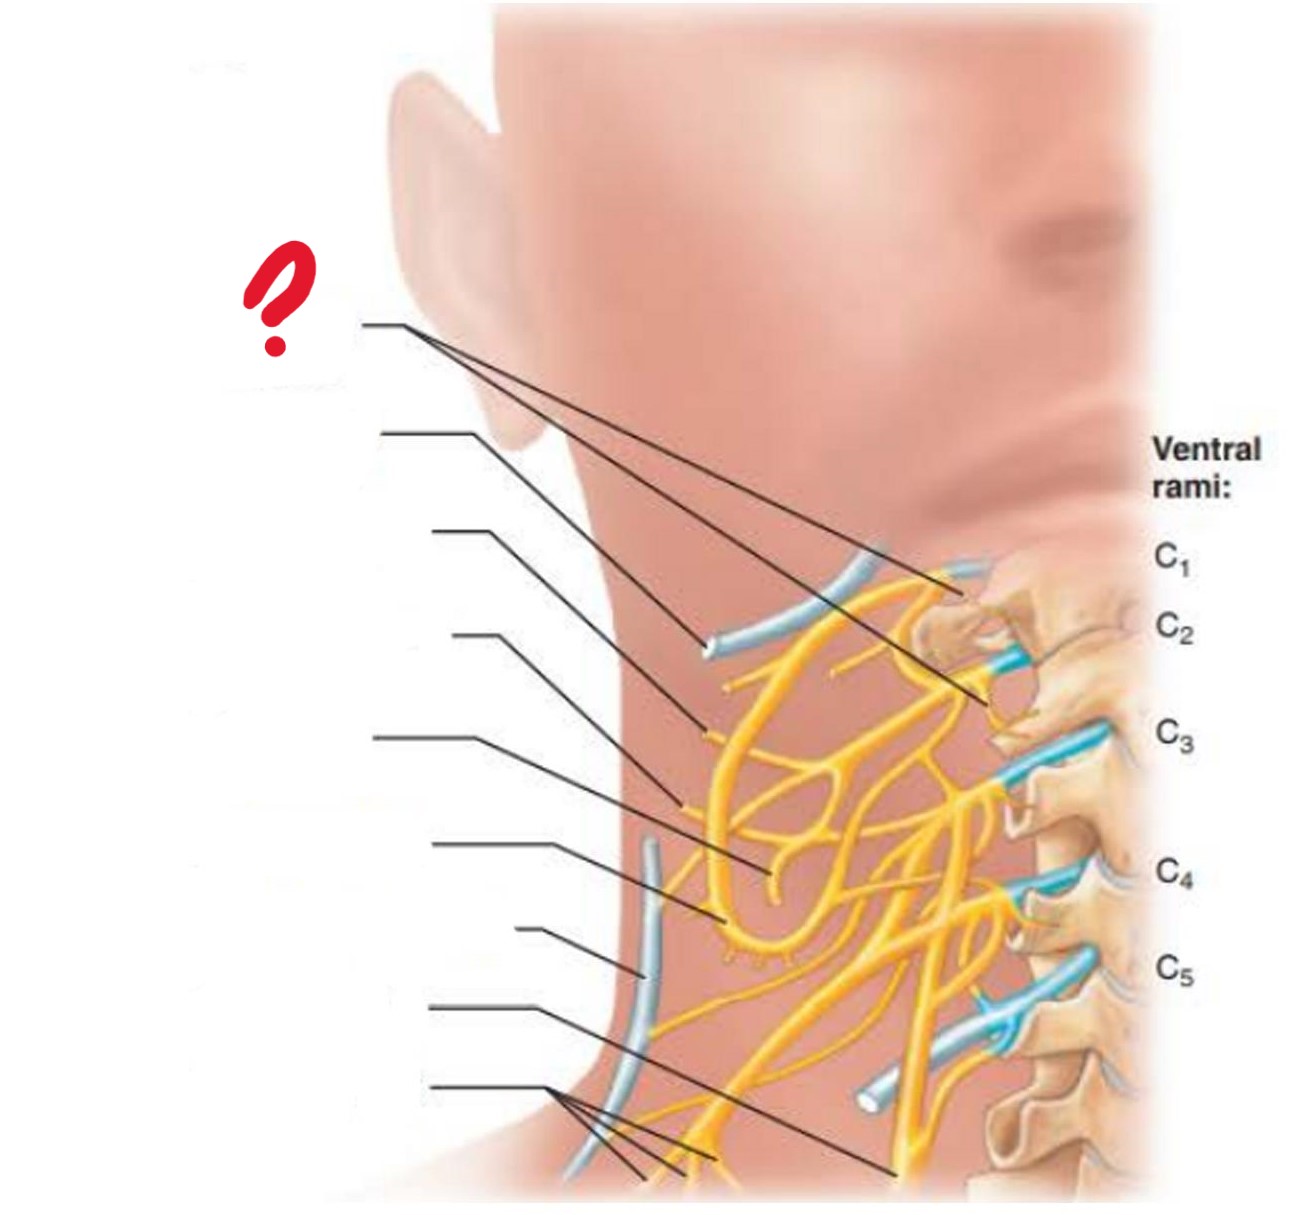

cervical plexus

C1-C4

major nerve: phrenic nerve

segmental branches

hypoglossal nerve (12)

lesser occipital nerve

greater auricular nerve

transverse cervical nerve

ansa cervicalis

accessory nerve (11)

phrenic nerve

supraclavicular nerves